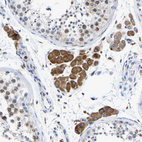

Immunohistochemistry analysis in human small intestine and testis tissues using HPA018884 antibody. Corresponding P4HB RNA-seq data are presented for the same tissues.